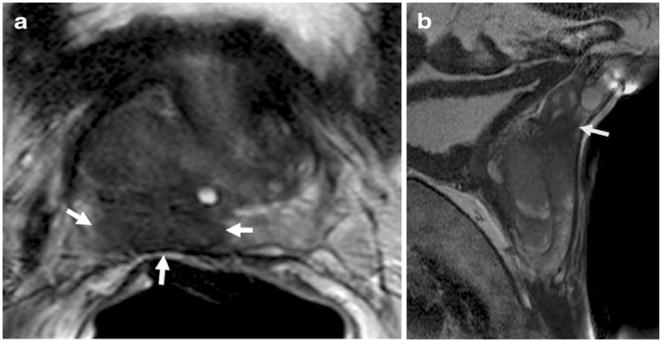

Fig. 3.

Axial and sagittal T2-weighted MR images of a 58-year-old man with prostate cancer demonstrate a big peripheral zone tumor (white arrows), which obliterates the right rectoprostatic angle suggesting extracapsular extension (a) and extends superiorly and invading seminal vesicles (arrow) (b). T Tesla